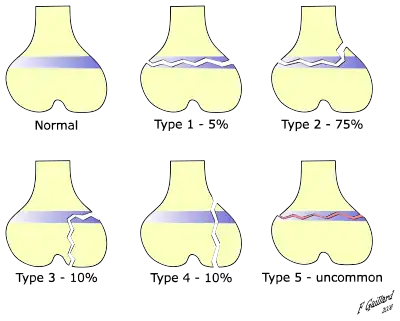

There are nine types of Salter–Harris fractures; types I to V were originally described,[3] and types VI to IX were added subsequently:[5]

- Type I – transverse fracture through the growth plate (also referred to as the "physis"):[6] 6% incidence

- Type II – A fracture through the growth plate and the metaphysis, sparing the epiphysis:[7] 75% incidence, takes approximately 12-90 weeks or more in the spine to heal.[8]

- Type III – A fracture through growth plate and epiphysis, sparing the metaphysis:[9] 8% incidence

- Type IV – A fracture through all three elements of the bone, the growth plate, metaphysis, and epiphysis:[10] 10% incidence

- Type V – A compression fracture of the growth plate (resulting in a decrease in the perceived space between the epiphysis and metaphysis on x-ray):[11] 1% incidence